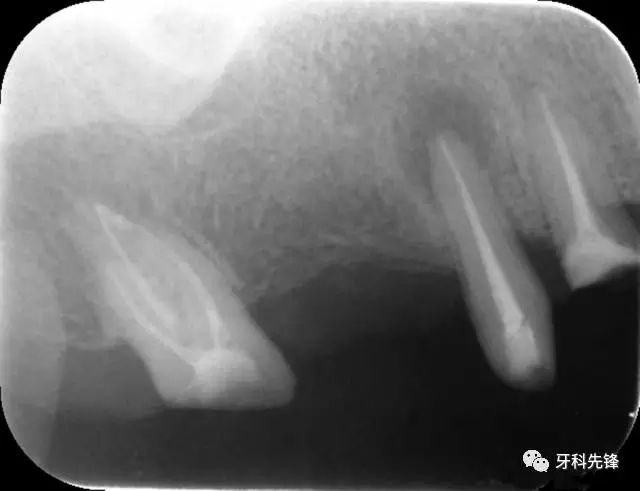

圖18 14  15   三個(gè)月后X光片(根尖陰影減?。?/p>

640.webp (22).jpg